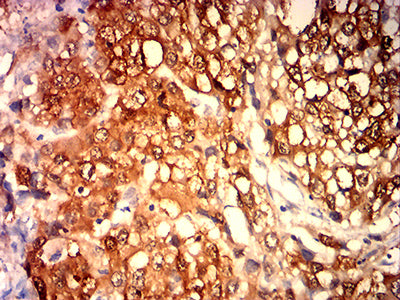

![MAGEA4 Mouse mAb[63896]](https://img1.dxycdn.com/p/s14/2025/0922/781/2952078590916699691.jpg)

Immunohistochemical analysis of paraffin-embedded human liver cancer tissues using MAGEA4 mouse mAb with DAB staining.